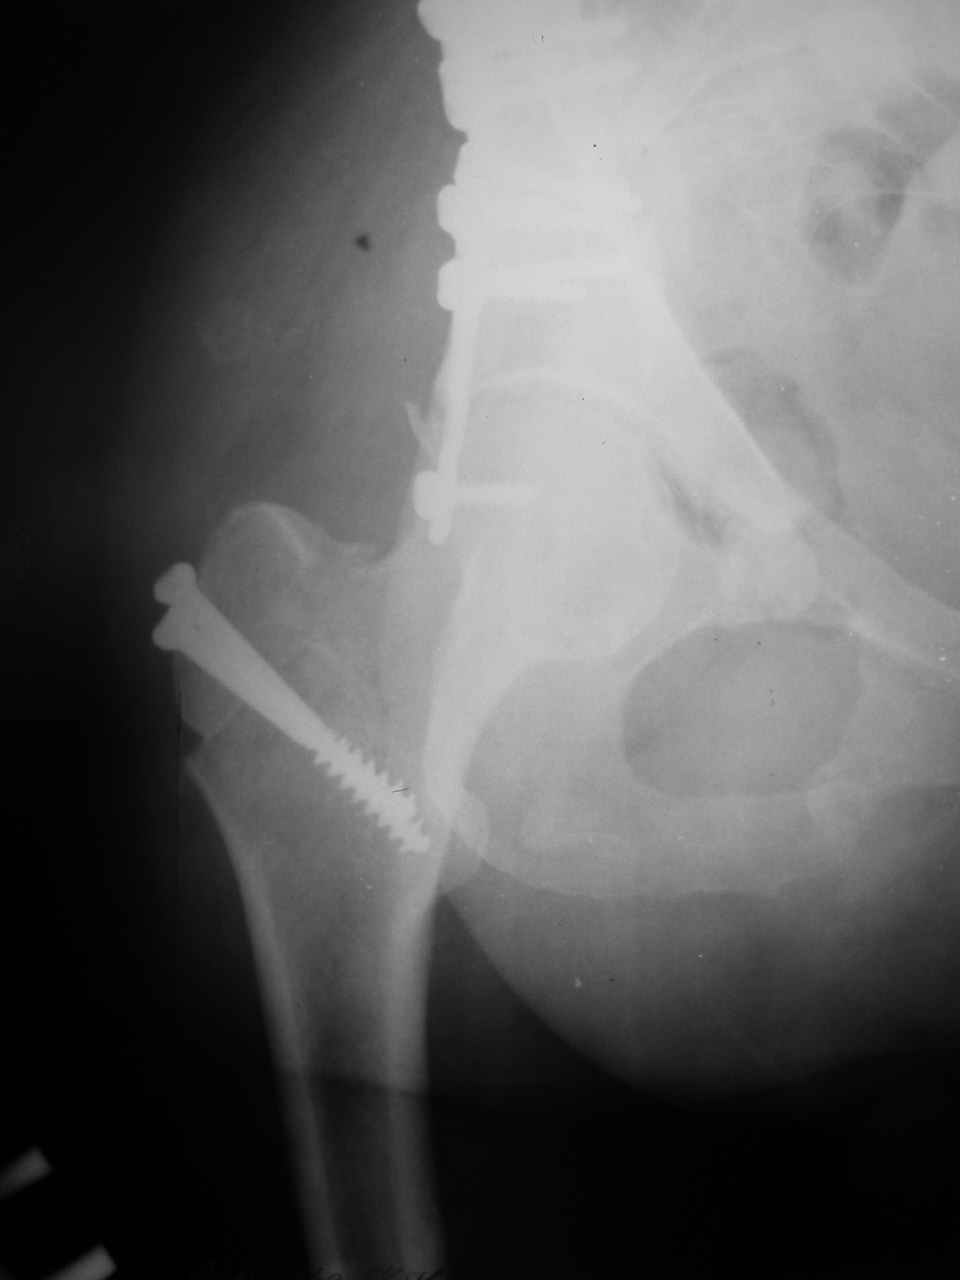

Сложностью, ассоциативностью характера перелома, я бы с радостью воспользовался мининвазивной перкутанной фиксацией винтами, но боюсь, что результат был бы ещё хуже, техникой непрямой репозиции перелома не владею, поэтому пытаясь получить анатомичную впадину приходится широко открывать, по крайней мере пока, а дальше буду пытаться уменьшать пространство...

Илеофеморальный доступ не совсем передний и сравнительно с илеоингвинальным, и Кохера-Лангенбека открывает весь наружный таз кроме самых передних отделов лонных костей, фиксацию которых я не ставил в задачу. Обширность диссекции, большая длительность операции и более высокий риск гетерооссификации - отрицательные моменты в обмен на возможность легче ориентироваться.

Вопрос доступа к вертлужной впадине при остеосинтезе задача не простая. Конечно, у Летурнеля и Тайла всё давно описано, нам остается только брать на вооружение. Но сами понимаете, что не бывает двух одинаковых ситуаций, поэтому в каждом случае вопрос решается сугубо индивидуально. Наша главная цель - восстановить анатомию с нанесением минимальной дополнительной травмы тазобедреннному суставу, думаю с этим никто не поспорит. Расширенный илиофеморальный доступ уж слишком травматичен (как сказал один коллега "таз лежит отдельно, больной отдельно").Стоит ли делать из пациента анатомический препарат для того чтобы легче ориентироваться. Да и нужно ли собирать всю "мозаику"? Мы применяли при таких операциях своеобразную операционную хитрость - сначала устраняли грубое смещение крыла под гребнем с фиксацией так называемой "плавающей" пластиной (временно фиксированной на двух винтах)- доступ или продлевали боковой, или делали небольшой дополнительный разрез над гребнем. Это позволяло устранить грубое смещение и захождение отломков тела повздошной кости, что значительно облегчало репозицию и остеосинтез впадины над сводом. Основное внимание конечно же уделяли нагружаемому задне-верхнему отделу. Сообщите ваш адрес, пришлю схемы и рентгенограммы.